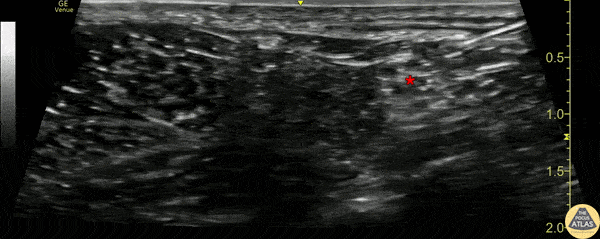

30s M presented to the ED with a large anterior shin wound after being struck by a car. A popliteal sciatic nerve block was performed for analgesia with good effect, and the patient was able to have his wound irrigated and repaired. In this clip, the sciatic nerve (*) is first seen superficial to the pulsating popliteal artery, and then anesthetic can be seen being injected within the sciatic nerve sheath (Vloka’s sheath). Dr. Sabrina Kaplan, PGY3 Denver Health Residency in Emergency Medicine